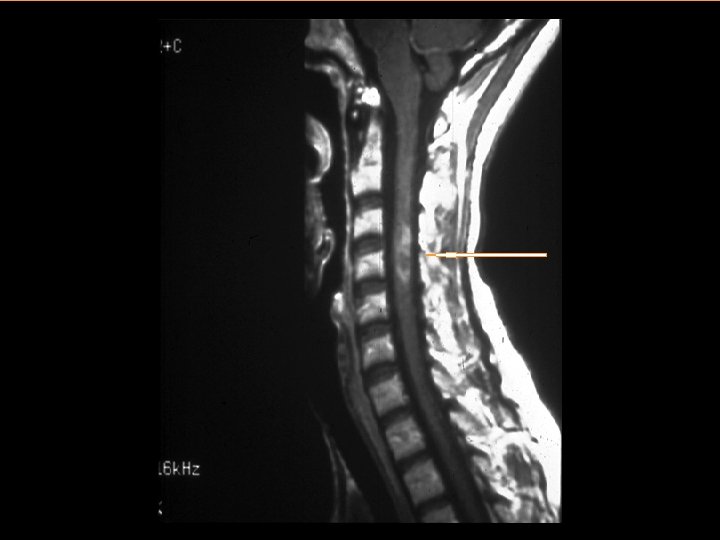

Diagnosing MS • MS is a clinical diagnosis – Signs and symptoms – Medical history • Paraclinical tests provide support – Magnetic resonance imaging – Spinal fluid – Evoked potentials • Diagnostic criteria: – Dissemination in time and space: evidence that damage has occurred in at least two separate areas of the CNS at different points in time – There must be no other explanation

Conventional MRI in MS Clinical Practice FLAIR T 2 BOD* T 1 precontrast T 1 Gd postcontrast Disease Activity† Black Holes† The strongest correlation with progression of disability *Reprinted with permission from Miller DH et al. Magnetic Resonance in Multiple Sclerosis. Cambridge: Cambridge University Press; 1997. †Reprinted with permission from Noseworthy JH et al. N Engl J Med. 2000; 343: 938 -952. Copyright © 2003 Massachusetts Medical Society. All rights reserved.

Clinically Isolated Syndrome (CIS) • A first neurologic event suggestive of demyelination • Individuals with CIS are at high risk for developing clinically definite MS if the neurologic event is accompanied by multiple, clinically silent (asymptomatic) lesions on MRI typical of MS